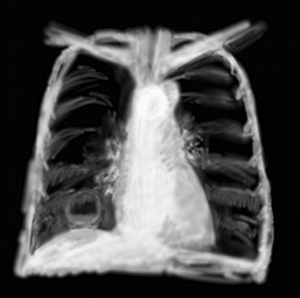

RP pneumonie type PFLA

On a déjà vu l’aspect des pneumopathies infectieuses alvéolaires bilatérales et interstitielles. La pneumopathie infectieuse la plus classique finalement c’est un infiltrat alvéolaire plutôt bien limité, caricaturalement la pneumonie franche lobaire aiguë à pneumocoque. Elle remplit un lobe de blanc tout en laissant de petites trainées noires qui correspondent aux bronches (bronchogramme aérique).

Le problème c’est que ces pneumonies sont en fait sous cet aspect radiologique quand elles sont «mûres», et qu’avant 48h, bien souvent radiologiquement il n’y a rien, alors même que cliniquement on entend déjà les crépitants. Je ne ferai l’affront à personne de parler du souffle tubaire, je l’ai déjà entendu mais il ne faut pas trop compter dessus